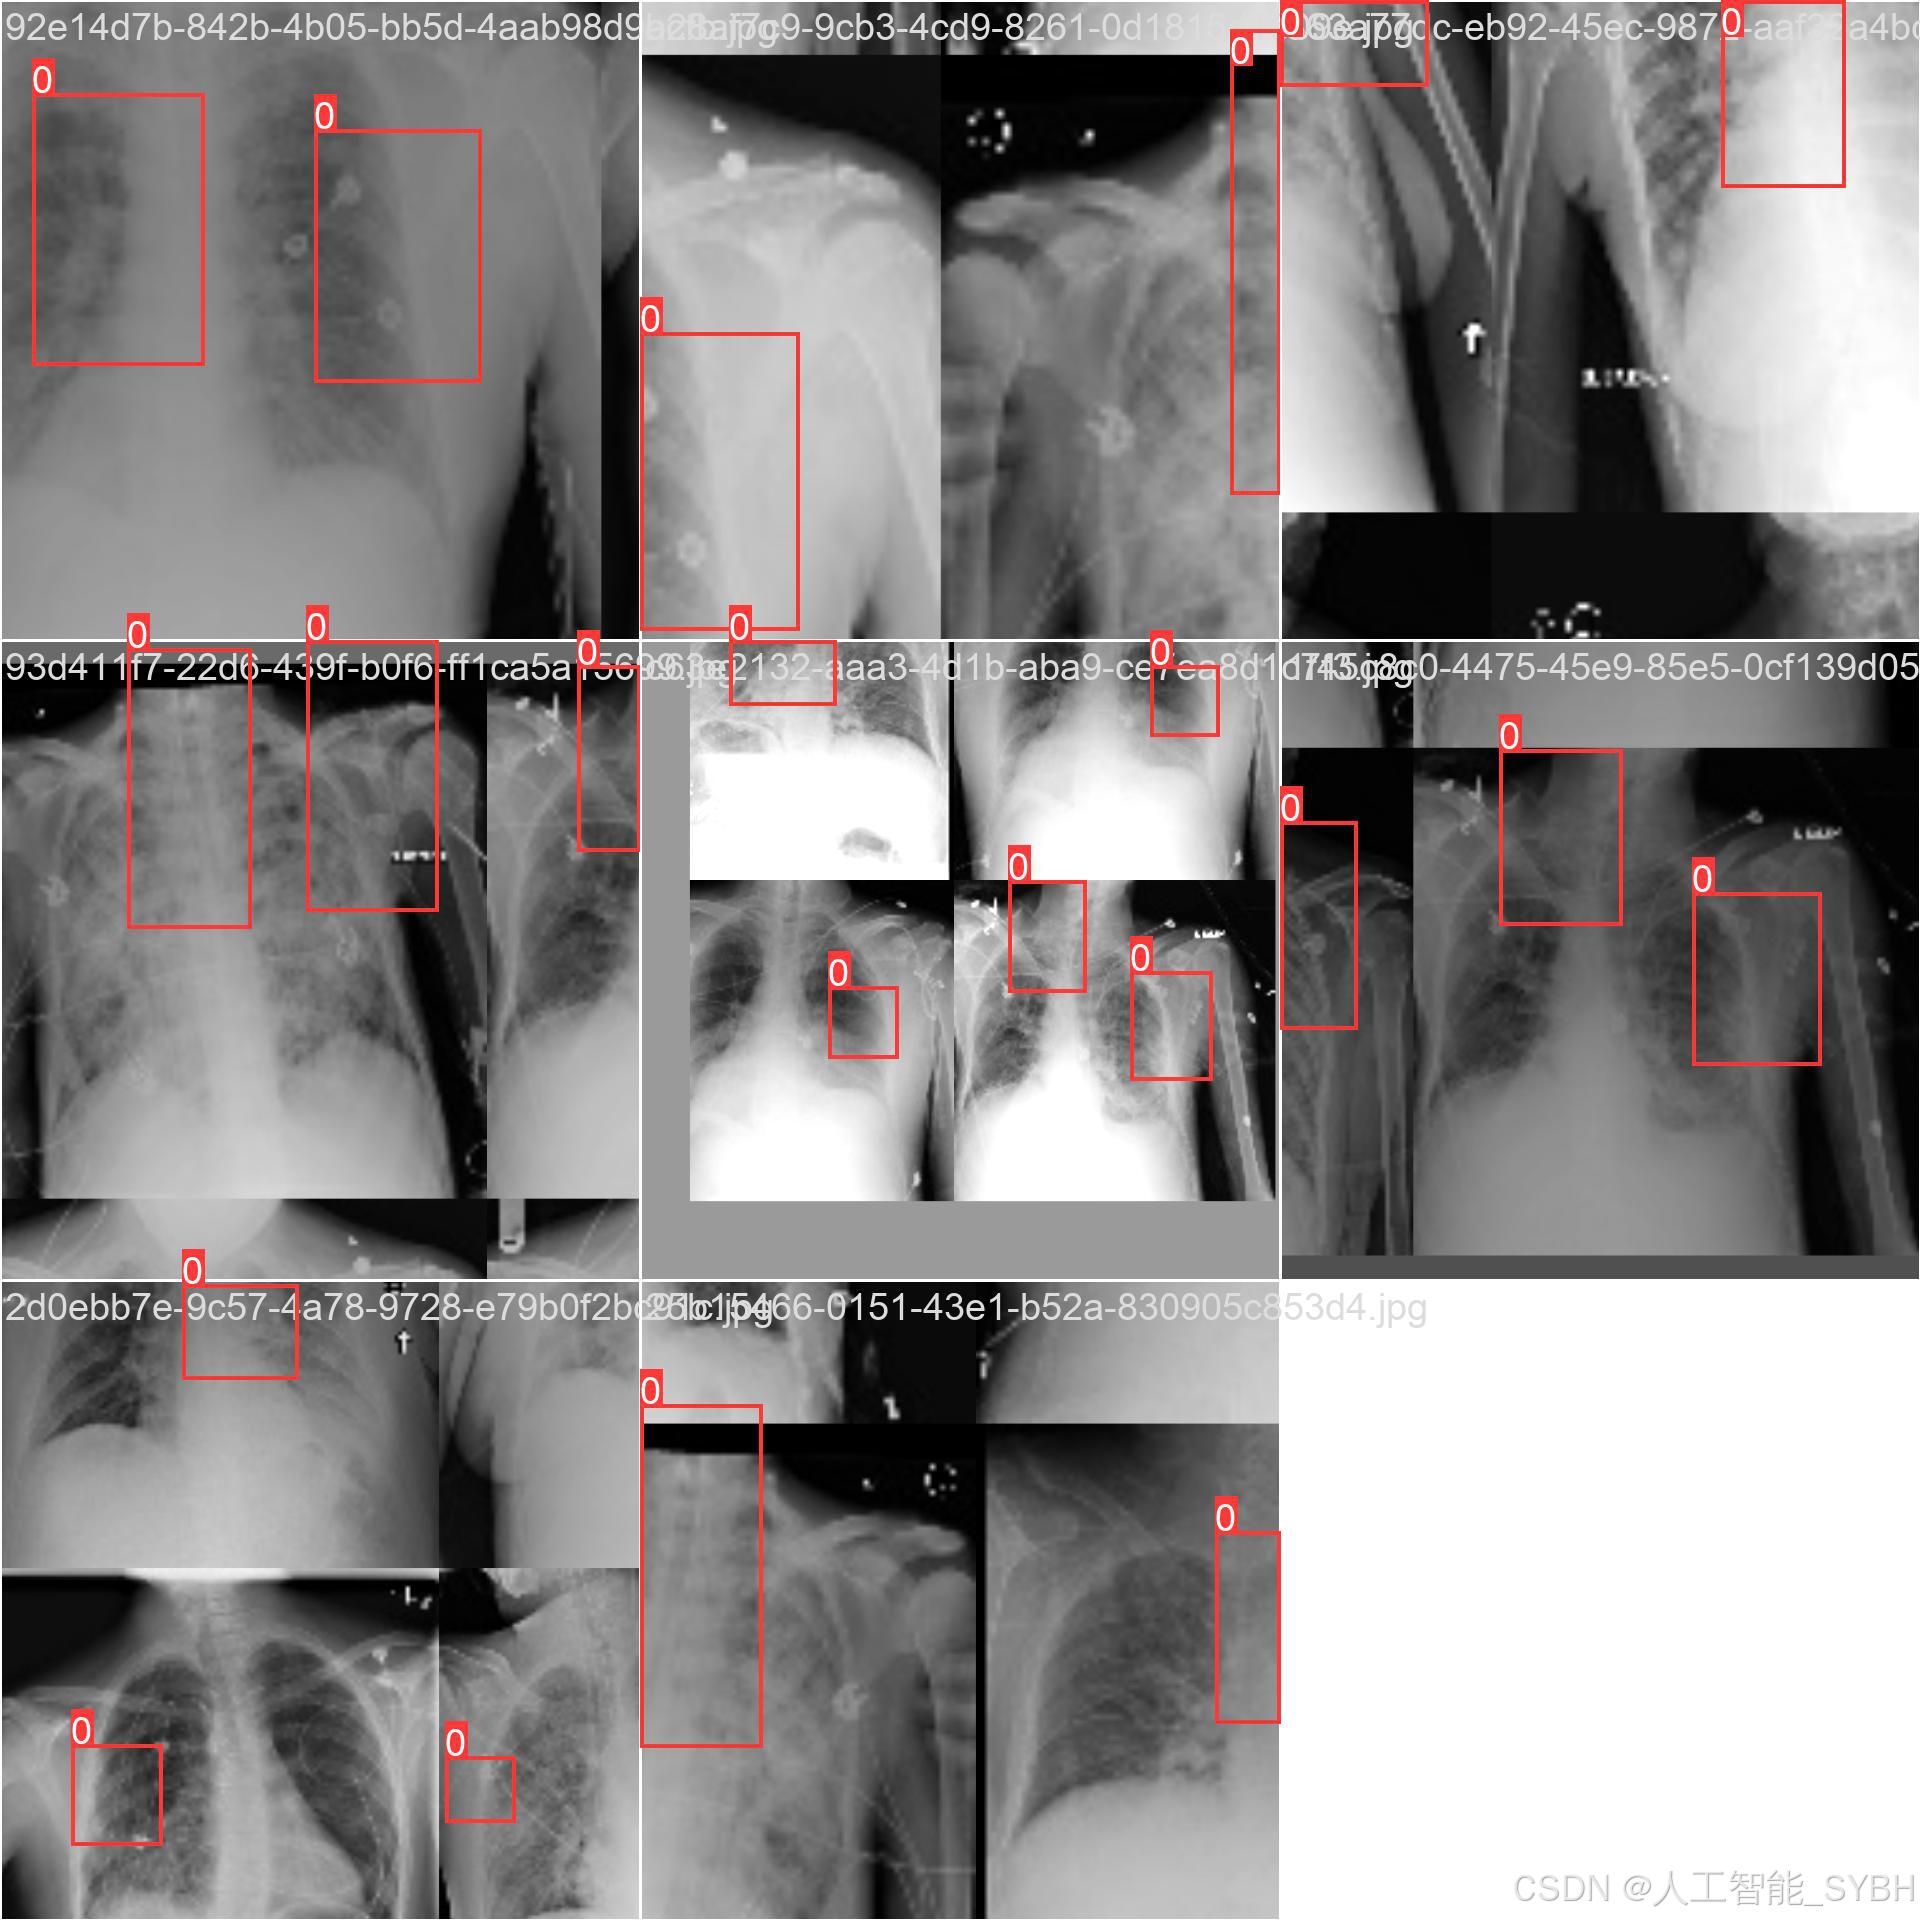

数据集名称: 肺炎检测数据集

数据集内容:

类别数量 (nc): 1类

类别名称: ['Pneumonia']

Pneumonia: 肺炎

数据集规模:

训练集: 3772张图像

验证集: 539张图像

测试集: 1078张图像

数据来源:

数据集通过收集医院中的胸部X光片构建,涵盖了不同年龄段、性别和病情的患者,以确保模型的泛化能力。

数据标注:

每张图像中的肺炎区域均使用边界框(Bounding Box)标注,并标注对应的类别。

数据集特点:

多样性: 数据集包含不同患者的胸部X光片,覆盖了多种病情和拍摄条件。

高质量: 图像分辨率高,标注精确,适合深度学习模型的训练。